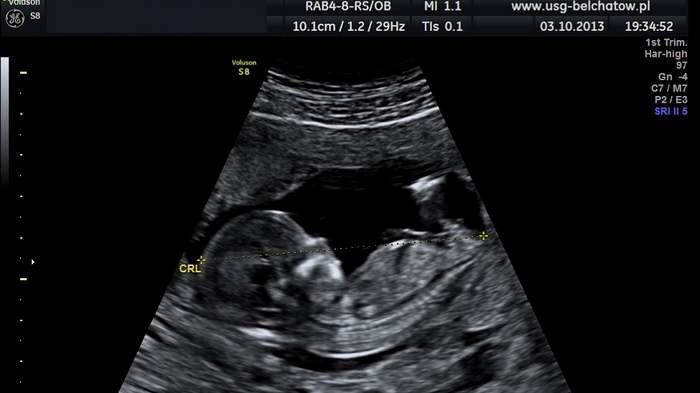

Satu-satunya petunjuk menentukan apakah bayi yang dikandung Raudiah benar kembar atau tidak, yakni dengan membaca hasil USG

Sebab, satu-satunya petunjuk menentukan apakah bayi yang dikandung Raudiah benar kembar atau tidak, yakni dengan membaca hasil USG dari 4 rumah sakit berbeda.

Raudiah memang melakukan pengecekan USG di 4 RS berbeda sebelum akhirnya melahirnya di RS Harapan Jayakarta dan hasil ke-4 USG itu menunjukkan Raudiah mengandung bayi kembar.